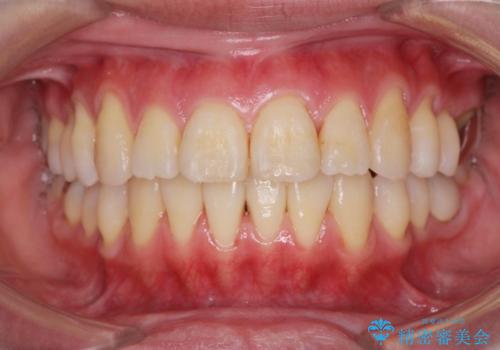

捻れた奥歯 突き出た前歯を治したい

時間はかかりましたが、捻れ、かみ合わせ、前歯の角度の改善が達成され満足いただくことができました。